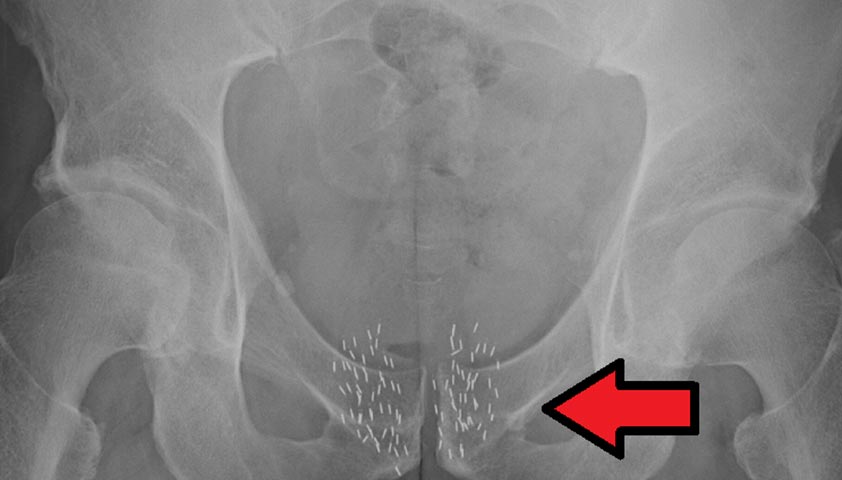

При низкодозной брахитерапии источники излучения «вживляются» в ткань предстательной железы и остаются там навсегда – до полного распада. На протяжении долгого времени этот вид брахитерапии применялся при раке предстательной железы наиболее часто. Для выполнения низкодозной брахитерапии наиболее часто используются изотоп радиоактивного йода – I125.

Многочисленные исследования показали, что при проведении низкодозной брахитерапии точность облучения может быть не очень высокой. Это происходит из-за смещения источников облучения, изменения размеров и формы предстательной железы, попадания источников излучения на прилежащие нормальные органы.

Для лечения рака предстательной железы используют «зёрна», которые излучают радиацию. Автор: James Heilman, MD, CC BY-SA 4.0, via Wikimedia Commons